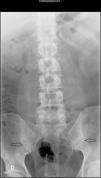

The patient in question is a 44 year old male with a history of alcohol abuse. He came to the consultation due to episodes of mono/oligoarthritis of the hands and ankles, recurring every week for 5 years, and inflammatory back pain of 10 years of evolution, with alternating buttock pain. He reported no other accompanying symptoms. Examination revealed the presence of arthritis of the right wrist, left 4th and 5th PIP with accompanying nodules. Laboratory tests showed uric acid 13.2mg/dl, ESR 44mm/h (0–20) CRP 15mg/l (<5mg/l) and a Mantoux test of 20mm. The remaining tests (CBC, TSH, CPK, rheumatoid factor, HLA-B27, anti-citrullinated-peptide antibodies, immunoglobulins, antibodies for hepatotropic virus, HIV, syphillis, Brucella, renal function, liver, urine sediment and uricosuria 24h) were normal. Chest, hands and feet X rays showed no pathological findings. The lumbar spine radiograph (Fig. 1) demonstrated left sacroiliitis stage II and right sacroillitis stage III. Examination with magnetic resonance imaging (MRI) of the lumbar spine was normal and sacroiliac MRI (Fig. 2) demonstrated irregularities and erosions in both sacroiliac joints observed in the T1 sequence. STIR detected subchondral bone marrow edema, markedly in the ilium and left sacral bone, with the right sacroiliac joint being less involved.